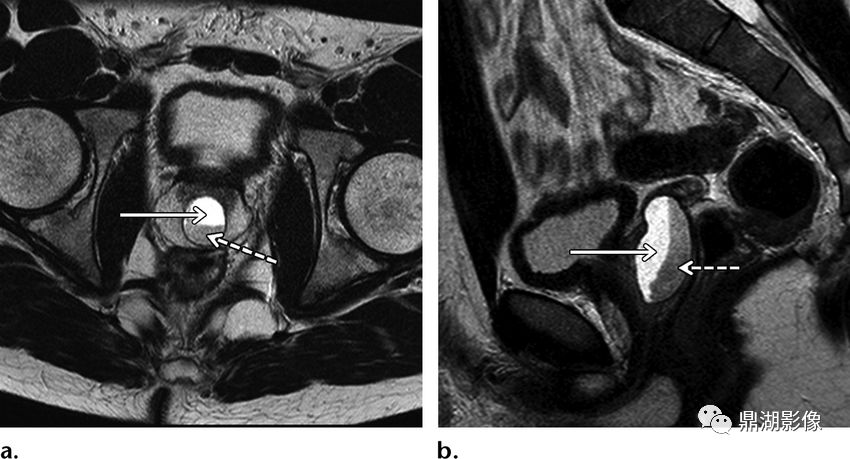

CT:囊肿表现为单房或多房的薄壁水样低密度病灶薄壁囊性肿块,边缘清楚光整。增强扫描未见强化。

病例二